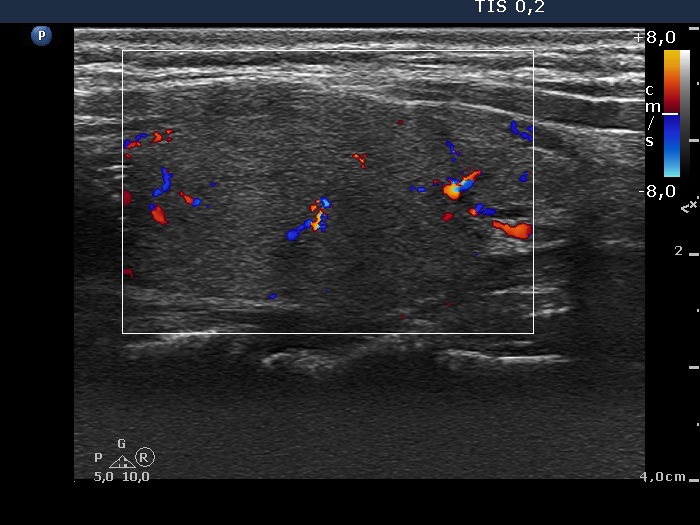

Benign nodular hyperplasia - Case 53. (ultrasonographic picture 8)

Left lobe, longitudinal scan, color Doppler mode. The vascularization is average, not specific.